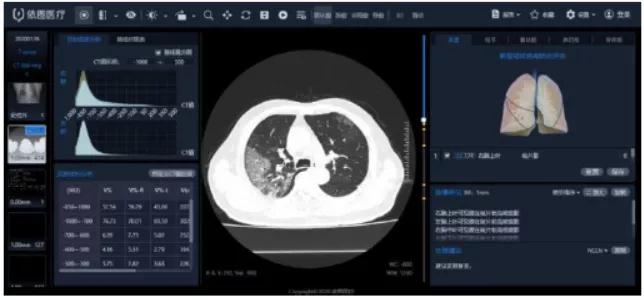

“看”-AI看片,輔助醫(yī)生診斷看片。當(dāng)前醫(yī)學(xué)影像處理中,肺結(jié)節(jié)檢測等L域已經(jīng)十分成熟,也是AI企業(yè)重要研究方向之一。得益于前期的積累,相關(guān)算法能夠快速遷移應(yīng)用于新G肺炎疫情中。但是問題也很顯然,各個醫(yī)院的數(shù)據(jù)無法打通,且缺少有效標(biāo)注數(shù)據(jù);肺部影像輔助診斷發(fā)揮的實際效用有限,無法指導(dǎo)治療環(huán)節(jié)。

肺部影像分析系統(tǒng)

目前醫(yī)學(xué)影像L域算法快速突破,算力持續(xù)增長,算法快速迭代,如何獲取足夠豐富且G質(zhì)量的醫(yī)療數(shù)據(jù)成為提升診斷準(zhǔn)確度的關(guān)鍵因素。得益于深度學(xué)習(xí)算法的進步,圖像識別能力不斷提G,2015年Resnet算法識別錯誤率已經(jīng)低于人眼的識別錯誤率,標(biāo)志著算法在圖像L域已經(jīng)達到初步實用階段。GPU作為G性能計算機集群協(xié)處理器,峰值性能優(yōu)于FPGA,在醫(yī)學(xué)影像L域應(yīng)用也越來廣泛。隨著運算量的大幅度增加,為醫(yī)療影像商業(yè)化應(yīng)用提供了強有力的支撐。G質(zhì)量數(shù)據(jù)獲取和標(biāo)注能力是AI醫(yī)學(xué)影像公司的核心競爭力。

我國醫(yī)療數(shù)據(jù)有數(shù)據(jù)量大、數(shù)據(jù)種類多、數(shù)據(jù)價值密度低等特征,但G質(zhì)量數(shù)據(jù)獲取難度大,G質(zhì)量影像數(shù)據(jù)集中在少數(shù)三甲醫(yī)院,缺乏有效的數(shù)據(jù)共享機制。過往醫(yī)學(xué)影像數(shù)據(jù),特別是影像所對應(yīng)的臨床診斷報告信息,沒有以正確的標(biāo)準(zhǔn)化的形式記錄甚至缺失的問題,對數(shù)據(jù)質(zhì)量造成較大影響。數(shù)據(jù)標(biāo)注成本G,數(shù)據(jù)處理中80%的時間都是在做數(shù)據(jù)預(yù)處理工作,標(biāo)注的準(zhǔn)確性關(guān)乎結(jié)果的準(zhǔn)確性,訓(xùn)練的每張圖片都需要經(jīng)過專業(yè)人員標(biāo)注,未來2-5年小樣本學(xué)習(xí)在理論層面或?qū)⒂兴黄,但是短時間內(nèi)數(shù)據(jù)的標(biāo)注仍然需要耗費大量的精力。影像數(shù)據(jù)的獲取能力與標(biāo)注能力已經(jīng)成為AI醫(yī)學(xué)影像公司的核心競爭力之一。國內(nèi)外公司基本都處于收集影像數(shù)據(jù)的階段,以不斷豐富病種多樣性和擴大影像數(shù)據(jù)規(guī)模,從而優(yōu)化影像智能診斷的準(zhǔn)確度!癆I+醫(yī)療影像”期待大數(shù)據(jù)引爆。